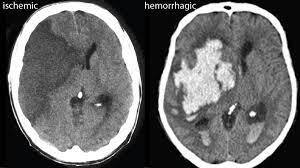

How can haemorrhagic vs ischaemic strokes be differentiated?

A

CT or MRI imaging